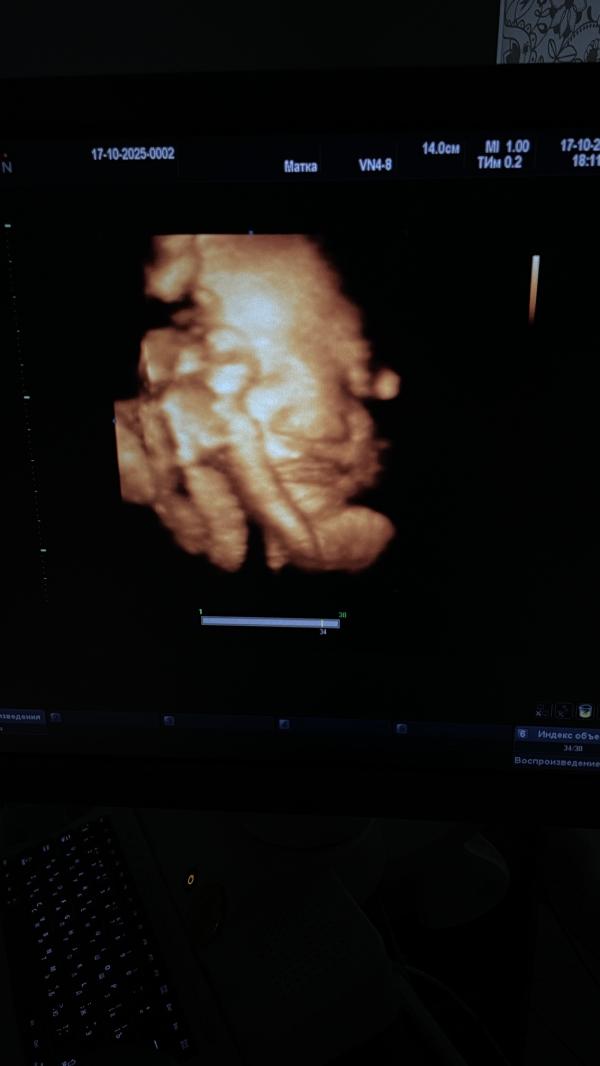

36 неделек и свидание с сыном 🩵

Всё узи закрывал рукой лицо 🫣 зато яйки на показ всем продемонстрировал во всей красе🤣

Вес 2750гр 🥰 (не судьба мне родить миниатюрного человека, похоже будет богатырь)